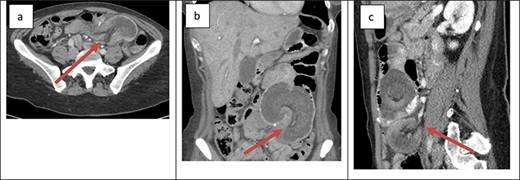

The first patient was a 36-year-old female with a history of type 1 plasminogen activator inhibitor deficiency, open Roux-en-Y gastric bypass 12 years prior, abdominoplasty with bilateral breast augmentation and chronic abdominal and back pain. She was 275 lbs at the time of her gastric bypass and 165 lbs at the time of presentation. The patient presented with a short history of new abdominal pain after a recent meal. No other associated symptoms were present upon presentation. Her vitals were within the normal limits and laboratory work was unremarkable. An abdominal ultrasound was obtained to evaluate for biliary disease, which revealed cholelithiasis without further evidence of acute process. Cross-sectional imaging revealed a small bowel obstruction secondary to small bowel intussusception at the jejunojejunal anastomosis (Fig. 1). The patient was taken emergently to the operating room for a laparoscopic lysis of adhesions and reduction of intussusception. In the operating room, ~60 cm of jejunum was found to be involved at the site of the jejunojejunostomy; after reduction, the involved bowel appeared viable so no formal resection or revision was performed. The patient’s post-operative course was uncomplicated. She was started on clear liquids on POD#1 and discharged home on POD#4. After discharge, the patient continued to experience episodic pain consistent with her chronic abdominal pain. Cross-sectional imaging ruled out further episodes of intussusception.

Cross-sectional imaging of displaying bowel and mesentery (arrow) intussuscepting into the JJ anastomosis on (a) transverse view, (b) coronal view and (c) sagittal view.

The presentation of intussusception is widely variable depending on the severity of the disease process. Common presentations include abdominal pain, nausea and vomiting, new palpable abdominal mass, lower GI bleeding and signs of sepsis. Intussusception can be diagnosed through various imaging modalities such as cross-sectional imaging, plain radiographs, small bowel series and ultrasonography. Cross-sectional imaging is believed to be not only highly sensitive but also reliable [3]. On cross-sectional imaging, intussusception appears as a complex soft tissue mass representing bowel telescoped onto itself often with an eccentric area of hypoattenuation within the mass representing the intussuscepted mesenteric fat [5]. The pathognomonic appearance is appreciated in Figs 1 and 2. Furthermore, the wall of the internalized loop of bowel can be observed within the dilated bowel when imaging is enhanced with intravenous contrast. Prompt diagnosis and surgical intervention are paramount in management of intussusception.